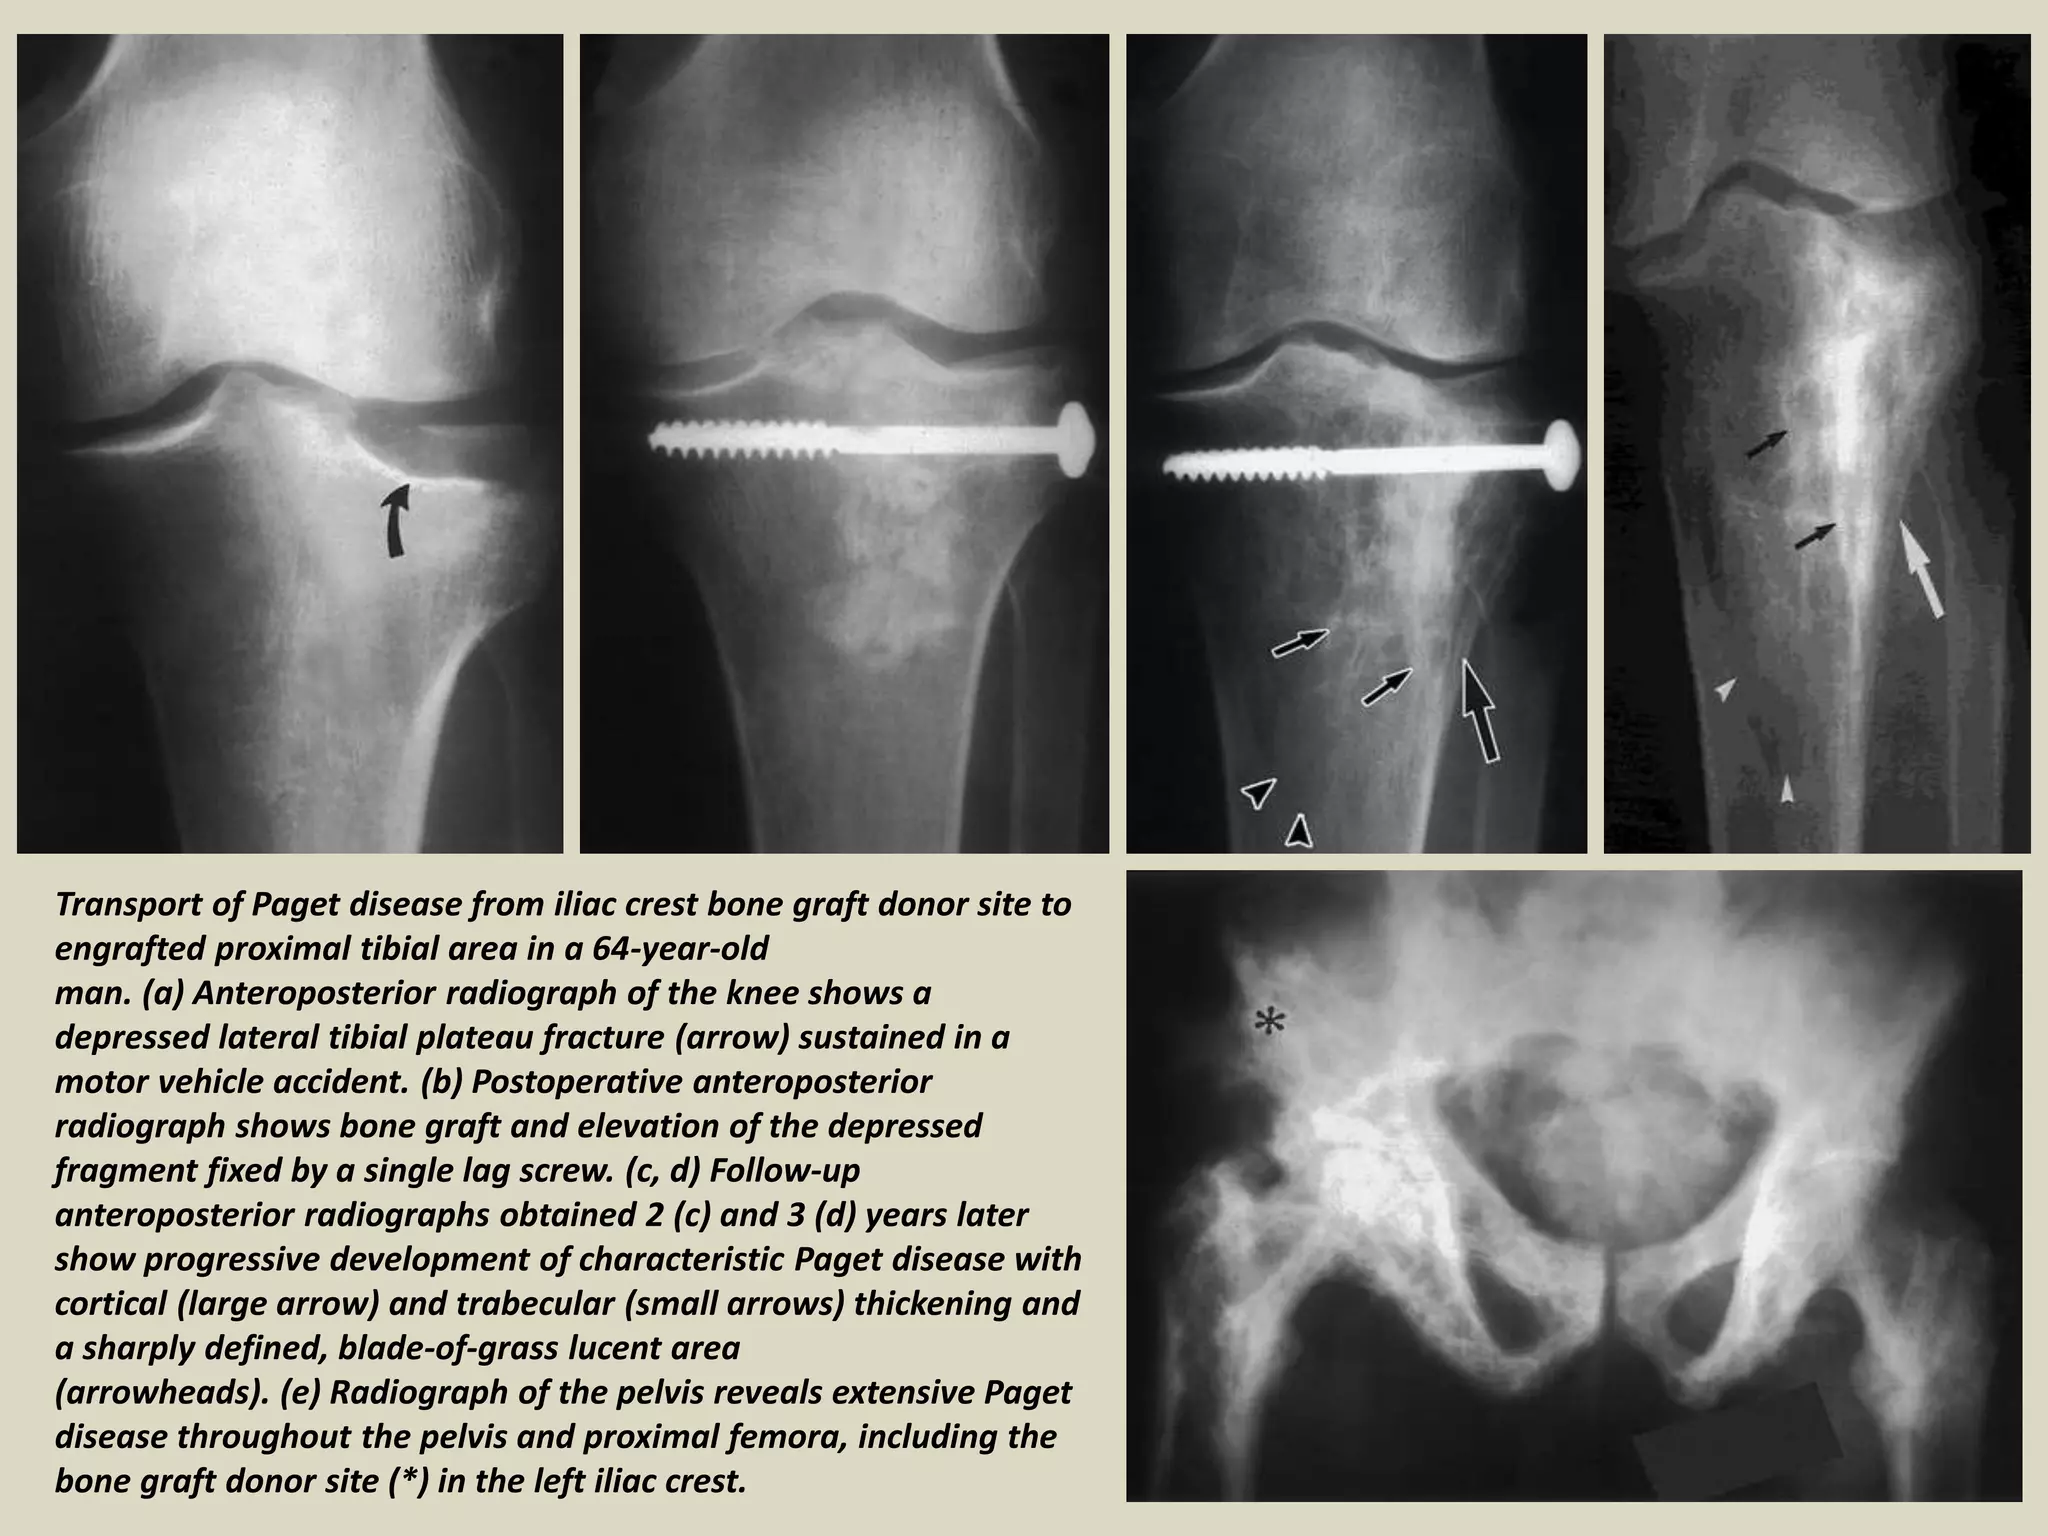

Transport of Paget disease from iliac crest bone graft donor site to

engrafted proximal tibial area in a 64-year-old

man. (a) Anteroposterior radiograph of the knee shows a

depressed lateral tibial plateau fracture (arrow) sustained in a

motor vehicle accident. (b) Postoperative anteroposterior

radiograph shows bone graft and elevation of the depressed

fragment fixed by a single lag screw. (c, d) Follow-up

anteroposterior radiographs obtained 2 (c) and 3 (d) years later

show progressive development of characteristic Paget disease with

cortical (large arrow) and trabecular (small arrows) thickening and

a sharply defined, blade-of-grass lucent area

(arrowheads). (e) Radiograph of the pelvis reveals extensive Paget

disease throughout the pelvis and proximal femora, including the

bone graft donor site (*) in the left iliac crest.